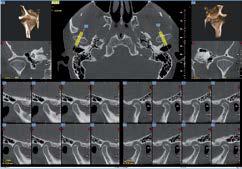

L’innovazione e la sicurezza sono due dei valori perseguiti dallo Studio Braconi a Terni, un punto di riferimento nell’ambito della radiologia 3D ortopedica grazie alla presenza del macchinario Newton 5G XL: si tratta dell’unico apparecchio nel Centro Italia che permette di eseguire una perfetta diagnostica per immagini in ortopedia e per la cervicale, oltre per le piccole articolazioni come seni paranasali, orecchie, colonna cervicale, gomito, polso, mano, ginocchio, caviglia e piede.

Nell’ambito della radiologia 3D ortopedica, il centro diagnostico utilizza il nuovissimo macchinario NewTom 5G XL, in grado di individuare con la massima precisione la presenza di fratture o lussazioni delle articolazioni, controllare la corretta guarigione di una frattura, valutare una lesione o una ferita causata da infezione, artrite o crescita anormale dell’osso.

Il tutto mediante una semplice e veloce scansione, grazie alla quale si otterranno diverse immagini in 3D ad altissima risoluzione e, per ottenere immagini ancora più nitide mediante un bassissimo dosaggio di radiazioni, gli esperti si avvalgono dell’innovazione racchiusa nella tecnologia Cone Beam.

Se con la radiologia tradizionale era necessario eseguire scansioni multiple, la novità introdotta dal macchinario NewTom 5G XL risiede nella capacità di fornire immagini ad alta risoluzione in un’unica scansione, mostrando nitidamente i dettagli delle articolazioni degli arti superiori e inferiori. Inoltre, a differenza della tecnologia 2D, la radiologia 3D ortopedica permette di individuare immediatamente alcune patologie come quella del metatarso, la quale richiede un allineamento visivo dedicato o una diagnosi delle micro fratture ossee.